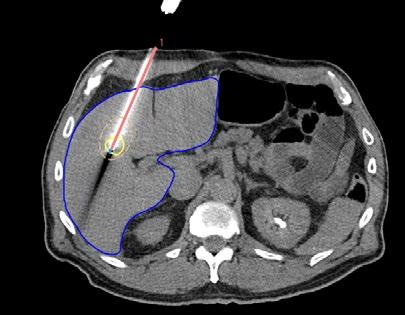

Vid leverablation sticks en nål in i tumören som sedan bränner bort tumören utgående från nålens spets. Med RayStation 2024B släpps stöd (image guidance) för att säkerställa att nålen är i rätt position så att hela tumören täcks av värmen. Metoden har utvecklats i samarbete med MDAnderson Cancer Centre som i en klinisk studie visat att denna teknik avsevärt förbättrar precisionen vid leverablation.

Under året lanserades en ny modul för bildstyrd leverablation i RayStation. Detta innebär att RaySearch nu tar ett steg utanför strålbehandlingsområdet. Leverablation är en behandlingsmetod där en nål förs in i tumören, varefter tumören förstörs genom värme genererad av mikrovågor eller högfrekventa radiovågor.

En utmaning med dagens metod är att tumören inte syns på de CT-bilder som tas efter att nålen placerats, och eftersom levern deformeras vid nålinsättning är det svårt att säkerställa att nålen är korrekt positionerad. Detta innebär en risk för att delar av tumören lämnas obehandlade.

Den nya modulen har utvecklats i samarbete med MD Anderson Cancer Center, som genomförde en klinisk studie med RayStation för att testa metoden. Studien var ursprungligen randomiserad, men bara efter att ett fåtal patienter behandlats kunde forskarna konstatera att precisionen förbättrades avsevärt med bildstyrningen och de valde därför att ta bort kontrollgruppen ur studien i förtid. Resultaten visar att metoden signifikant förbättrar precisionen vid leverablation.

Modulen i RayStation stödjer bildstyrd leverablation genom tre steg:

1. PLANERING – Innan nålen förs in tas en kontrastförstärkt CT-bild där tumören segmenteras. Användaren kan simulera nålinsättningen för att optimera placeringen.

2. MÅLSÖKNING – När nålen har förts in, men innan ablationen genomförs, tas en ny CT-bild utan kontrast. I denna bild syns nålen, men inte tumören. Genom deformabel bildregistrering i RayStation kan tumörens position från den tidigare kontrastförstärkta bilden överföras till den aktuella bilden, vilket gör det möjligt att verifiera att nålen är korrekt placerad. Om tumören inte täcks helt kan nålen justeras eller en extra nål planeras.

3. VERIFIERING – Efter behandlingen tas en postoperativ kontrastförstärkt CT-bild där ablationszonen syns som ett mörkare område. På denna bild segmenteras ablationszonen och tumören överförs deformabelt från planeringsbilden för att kontrollera att hela tumören har behandlats. Vid behov kan ytterligare behandling utföras.